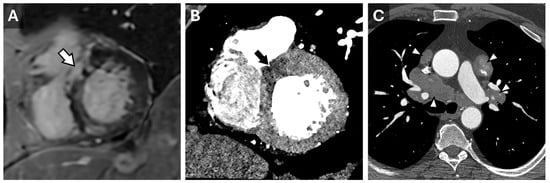

Traditionally measured via echocardiography or CMR, modern cardiac CT software can now estimate myocardial strain by analyzing pixel features, anatomic landmarks, and endocardial and epicardial borders (Figure 3 and Figure 4). However, CT-derived strain is limited by a lower temporal resolution, which may result in a weaker correlation to either MRI or Echo-derived strain values, particularly radial and circumferential measures. It is noted that, currently, neither radial nor circumferential values derived by either MRI or Echo are used in routine clinical practice due to high variability and low reproducibility; thus, this limitation with CT is currently more intellectual than clinical. In valvular disease, CT-derived strain has shown a moderate correlation with echocardiography (r = 0.6, p < 0.001), though it tends to underestimate strain values []. Despite this, CT provides a feasible method for strain assessment in advanced valve disease, complementing echocardiographic findings.

Figure 3. Cardiac MR Strain Evaluation. Static horizontal long-axis diastolic (A) and systolic (B) grid-tagged images from a cardiac MRI. Deformation of the grid as the myocardium contracts can be used to estimate strain.

Figure 4. Cardiac MR Strain Evaluation. Cine horizontal long-axis grid-tagged images from a cardiac MRI. Deformation of the grid as the myocardium contracts can be used to estimate strain.